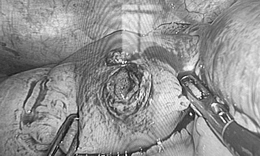

Việt kiều Mỹ 73 tuổi lựa chọn về Việt Nam phẫu thuật khối u đại tràng ác tính

Camera bệnh viện - 10/10/2025 14:55SKĐS - Việt kiều Mỹ 73 tuổi quyết định đến Bệnh viện Đa khoa Thủ Đức để thăm khám sau khi xuất hiện các dấu hiệu bất thường về đường tiêu hóa. Kết quả phát hiện khối u đại tràng ác nên nhanh chóng được phẫu thuật cắt bỏ.